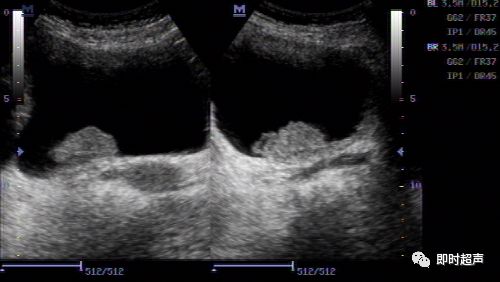

超声入门贴41-----膀胱癌

超声入门贴41膀胱癌